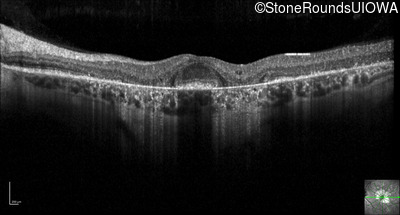

Optical Coherence Tomography - Right - 20/32 +2

Exemplar / OCT Stack

OCT Stack